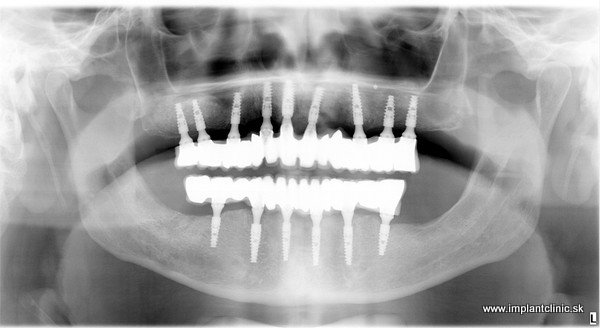

Druhá návšteva: implantácia. Z dôvodu oslabenej čeľustnej kosti sa naplánovalo do vrchnej čeľuste 9 zubných inplantátov, 6 zubných implantátov do sánky, dostavba kosti, sinus lift, extrakcie. Implantácia do oboch čeľustí prebehla počas jedného sedenia v lokálnej anestéze. Hneď po implantácii boli pacientovi nasadené fixne dočasné mostíky, ktoré sú pre maximálnu stabilitu a pevnosť vystužené titánovou konštrukciou.